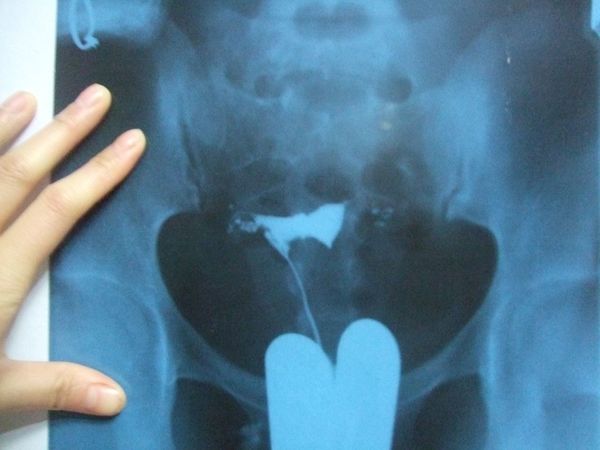

然后就可以起来了,起来后等待20分钟,20分钟后再次进去,这时候不需要脱*裤底**,直接有个类似做胸透的机器在小腹上,可能是拍片看碘油/碘水的扩散情况,这个过程很短暂,就结束了,造影到此完成。